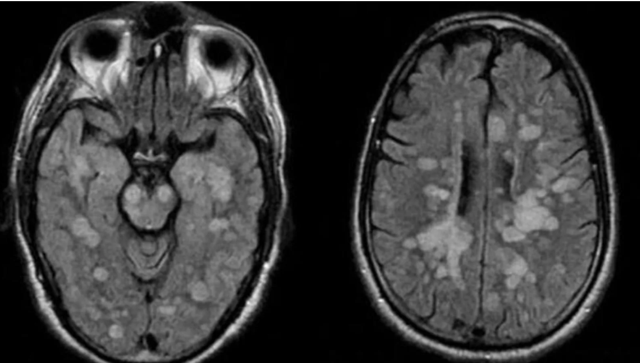

Talihsiz çocuğa vücudun bağışıklık sistemi kendisine saldırarak omurilik ve beynin şişmesine neden olan nadir bir akut yayılmış Ensefalit (ADEM) teşhisi konuldu. Avella’nın doktoru Dr. Michael Pitt, "Bu vakada yaşananların en büyük tetikleyicisi koronavirüs olmuştur” dedi.

Braun’un Akut dissemine ensefalomyelit (ADEM) santral sinir sisteminin immun aracılıklı bir bozukluğuna yakalandığı bildirildi. Tıp uzmanları, Haziran ayında koronavirüs ve ADEM arasındaki bağlantıyı kurmaya başladıklarını açıklamıştı. Uzmanlar, dünyada, koronavirüs atlatan kişilerde benzer vakalara rastladıkları konusunda uyarıyor.